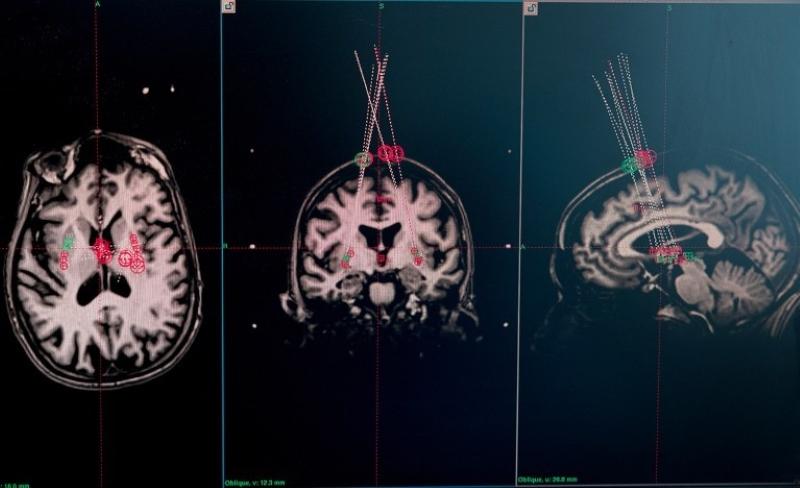

關于癲癇的研究同樣值得關注。在美國神經元治療公司開展的臨床試驗中,外科醫生借助干細胞療法,將干細胞整合到15名癲癇患者的神經回路中。移植一年后,其中兩名參與者嚴重癲癇發作的頻率幾乎降至零,且效果已經持續了兩年。其他大多數參與者的癲癇發作頻率也顯著降低。該公司報告稱,這一療法沒有明顯副作用,也沒有造成認知損傷。基于上述效果,包括神經元治療公司在內的團隊打造的“有效干細胞療法”,也被《麻省理工技術評論》評為2025年“十大突破性技術”之一。